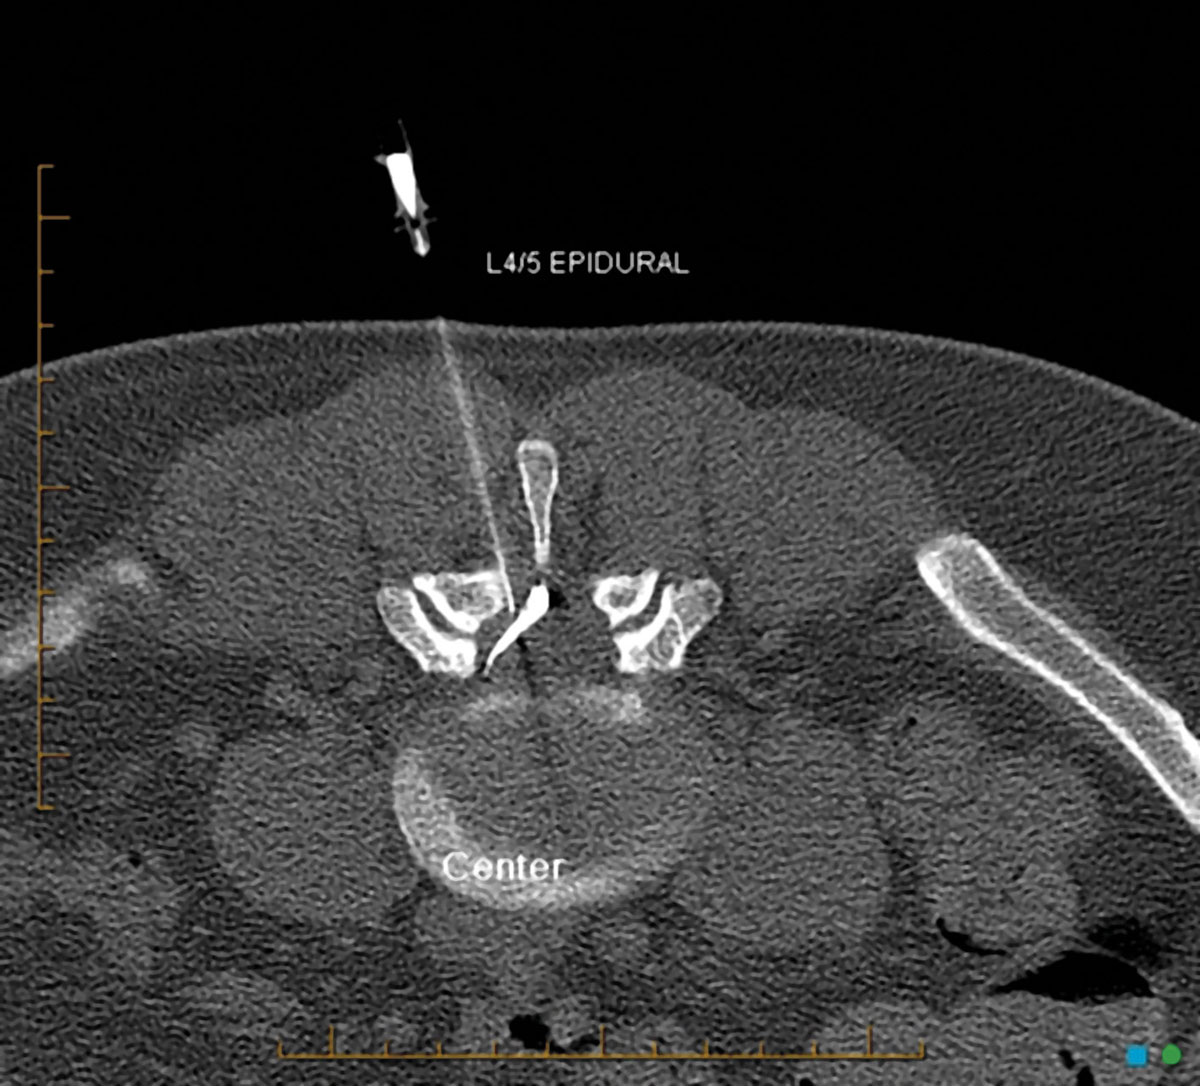

The burden of low back pain can respond to judicious use of non-surgical interventions by a radiologist.